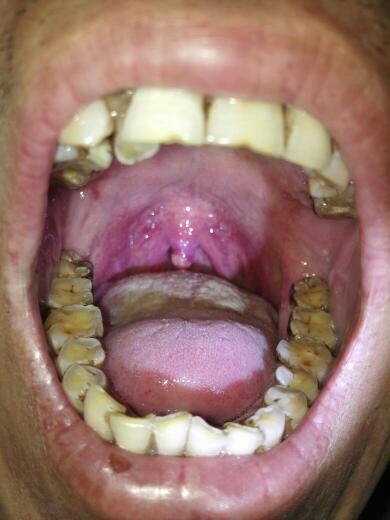

求救 求救求救 懂的医师 专家 麻烦耽误几分钟给我看一下 开始悬雍垂

问:急性咽炎,怎么治疗,悬雍垂水肿